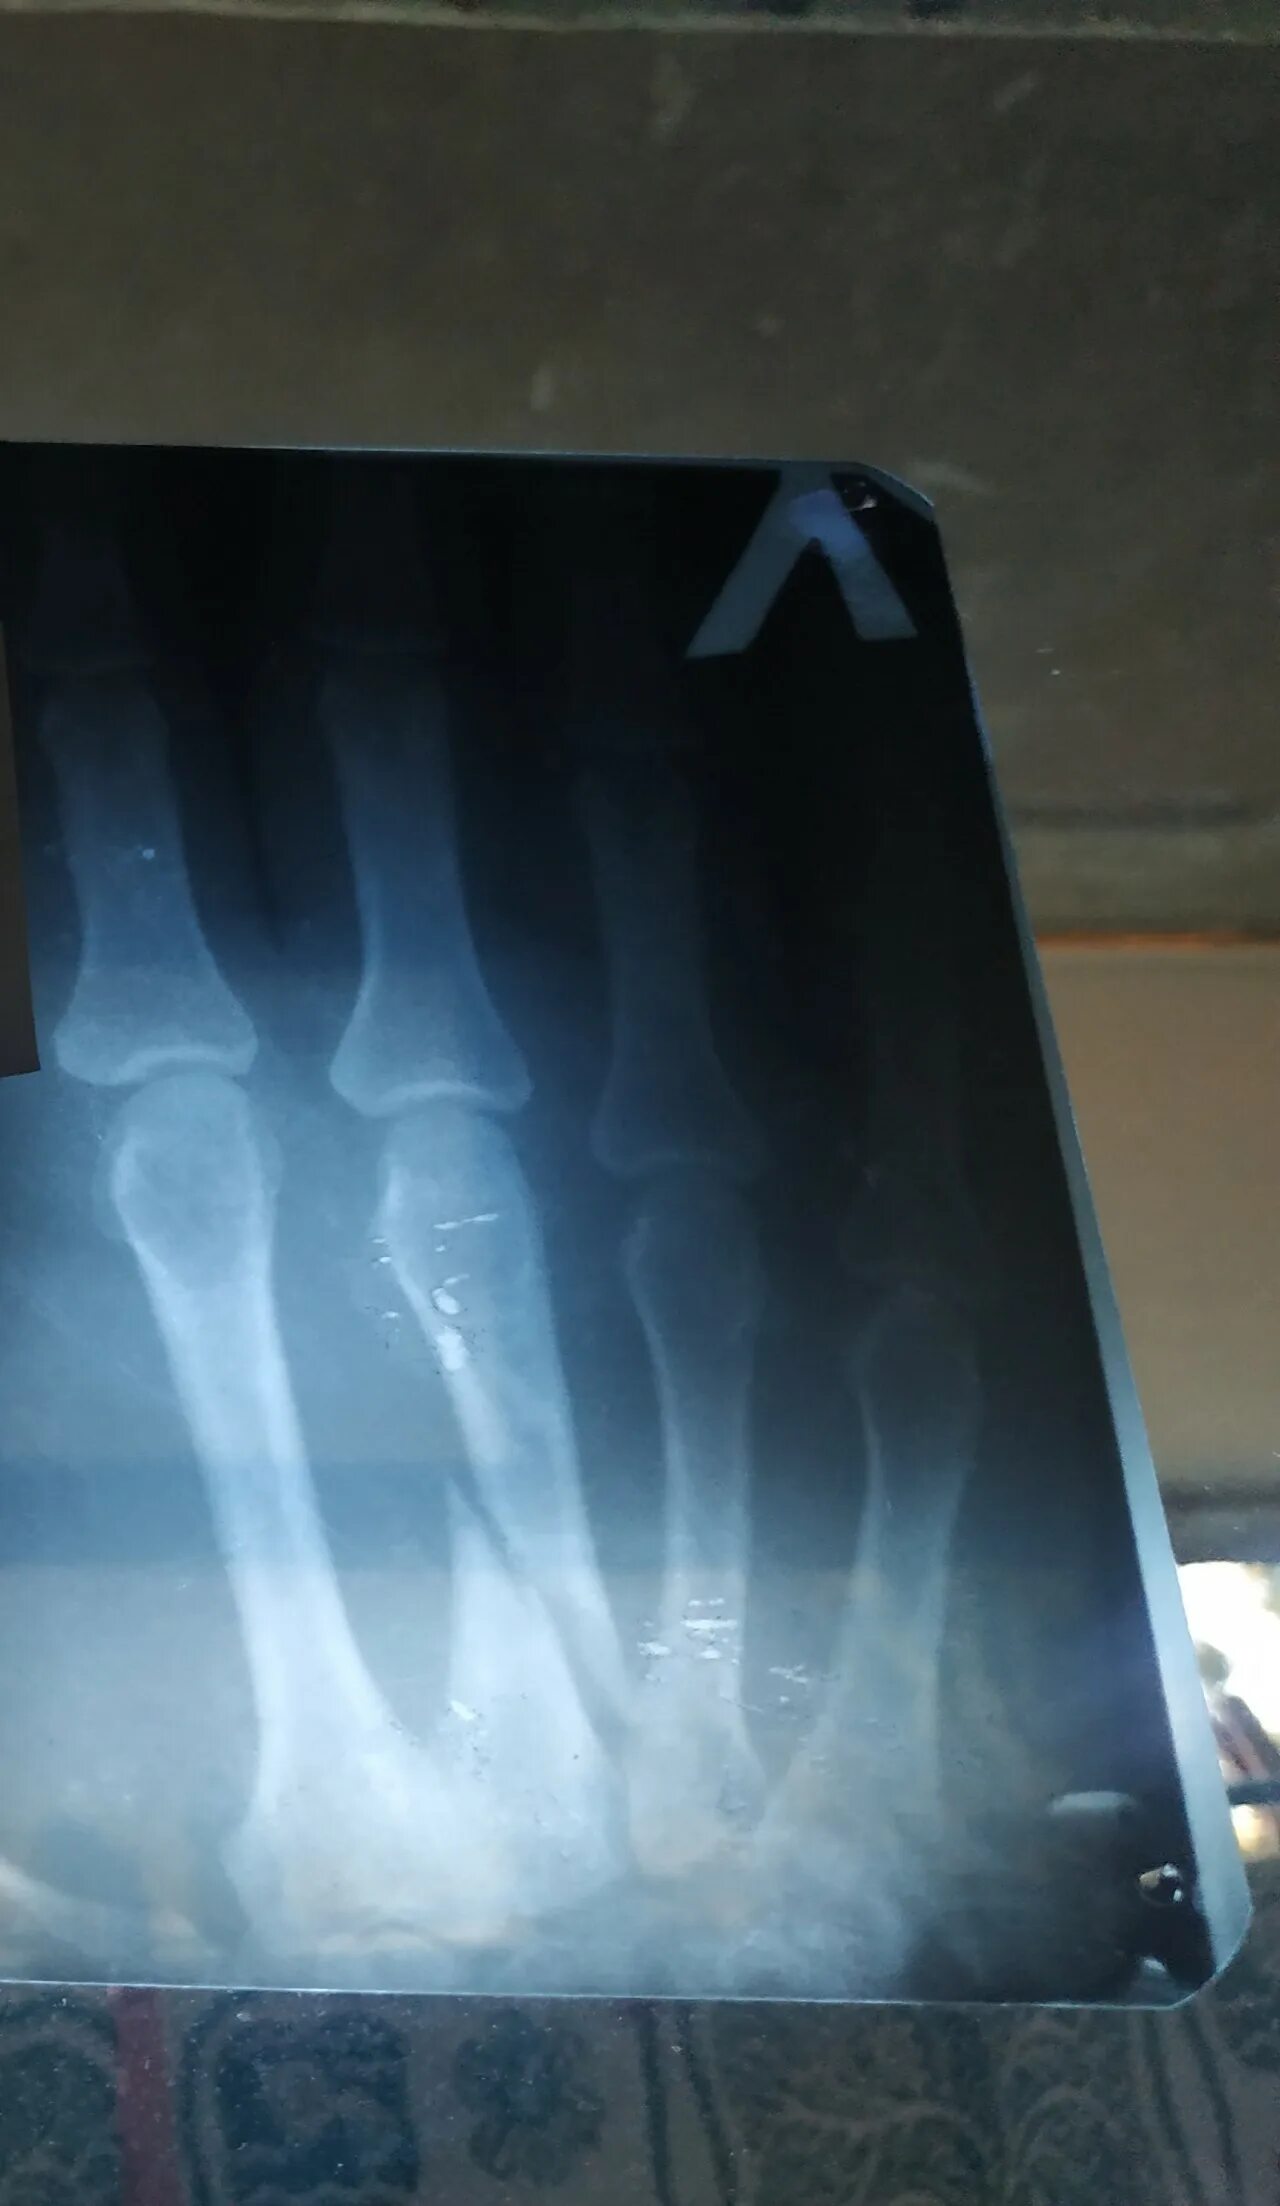

Перелом 3 пястной кости